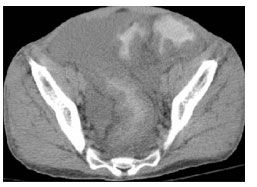

Two weeks later, he was again admitted with profound diarrhea and abdominal pain. He was hemodynamically unstable, with a pulse rate of 139 beats per minute and decreased urine output. His body temperature, respiratory rate, and oxygen saturation were within normal limits. Findings from the physical examination were remarkable for significant abdominal distention with tenderness and tympanism. An abdominal CT scan showed ascites and marked thickening of the colonic wall from the rectum through the cecum (Figure 1), suggestive of pancolitis. Results of an immunoassay test for C difficile toxins A and B in stool samples were persistently positive, but no specific tests were performed to isolate toxin A or B. His total white blood cell count was within normal range, with a relative lymphopenia. Blood and stool culture results were negative. A clinical diagnosis of toxic megacolon was made.

Figure 1.Abdominal CT scan without contrast from a 45-year-old HIV-infected man showing diffuse marked thickening of the colon.